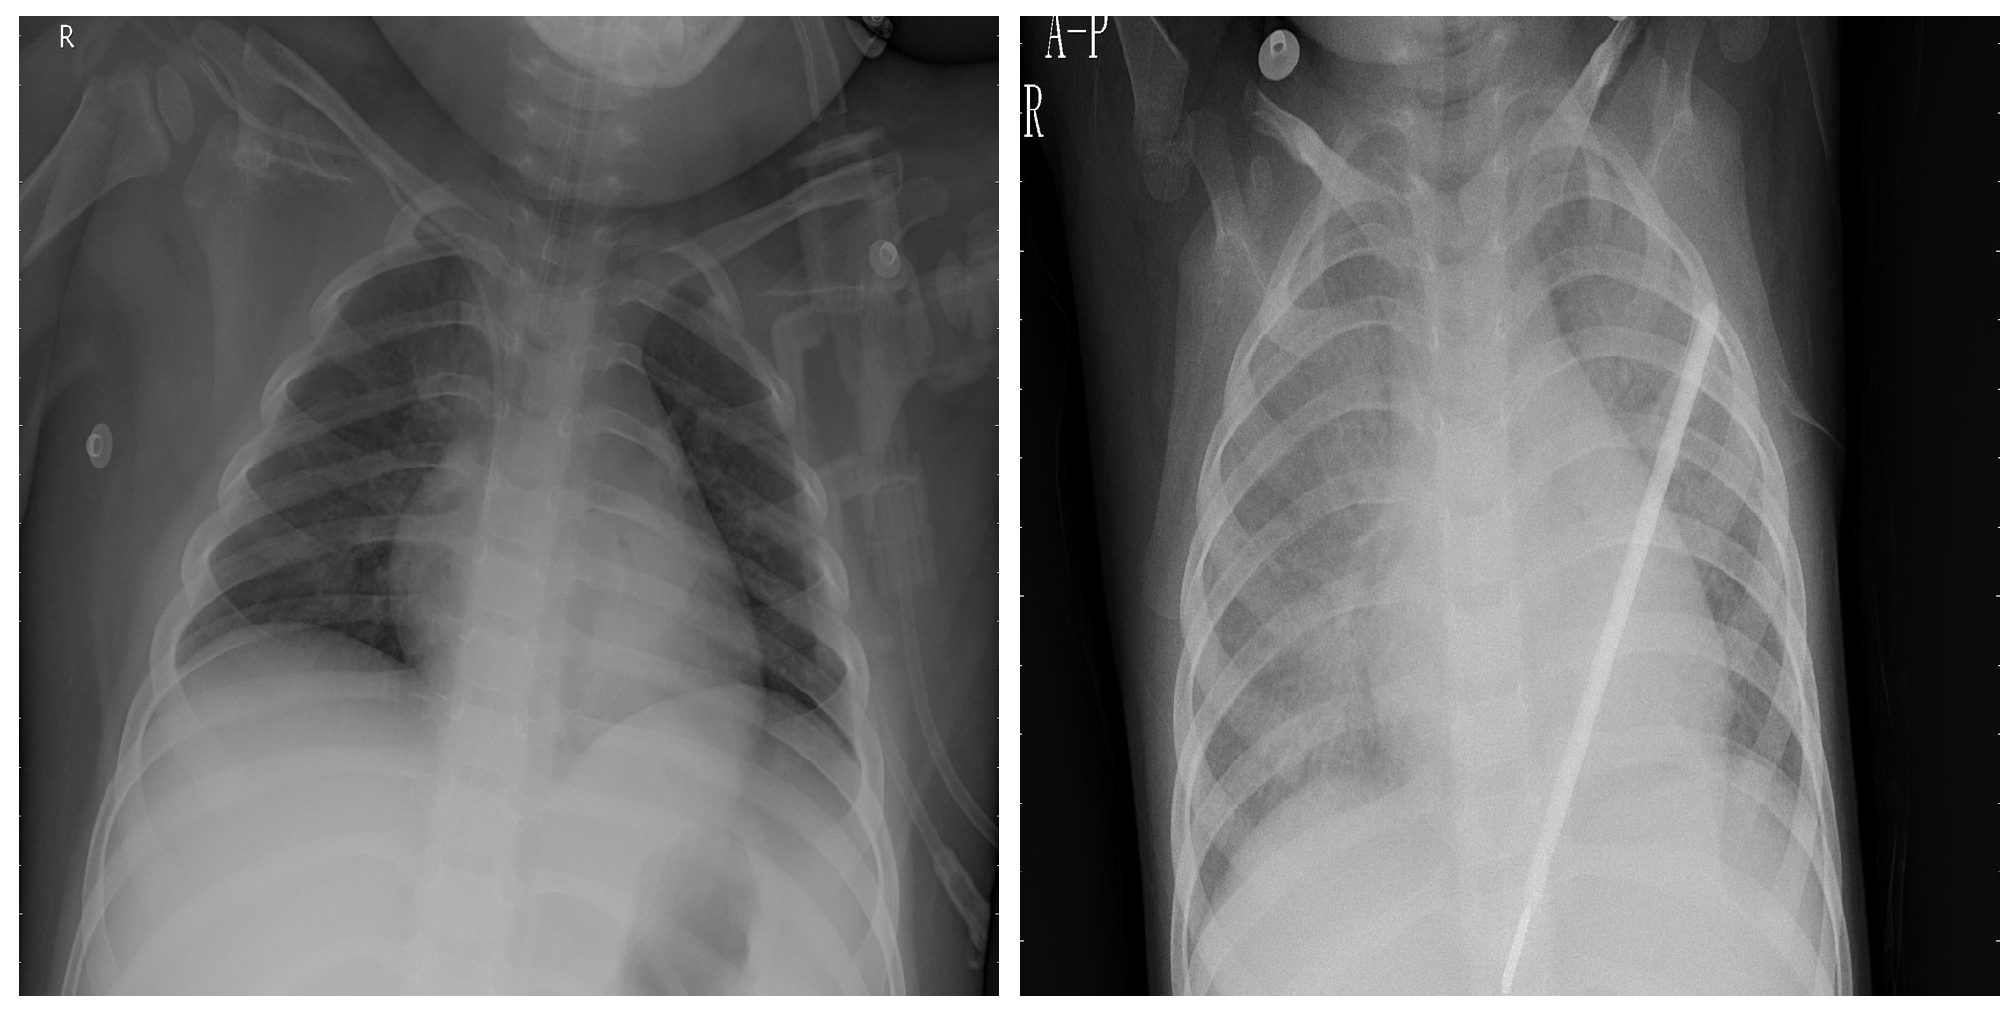

3.5. Chest X-ray Images Pneumonia (CXRIP)

3.6. Montgomery County X-ray

3.7. Shenzhen Hospital X-ray

3.9. Montfort Dataset